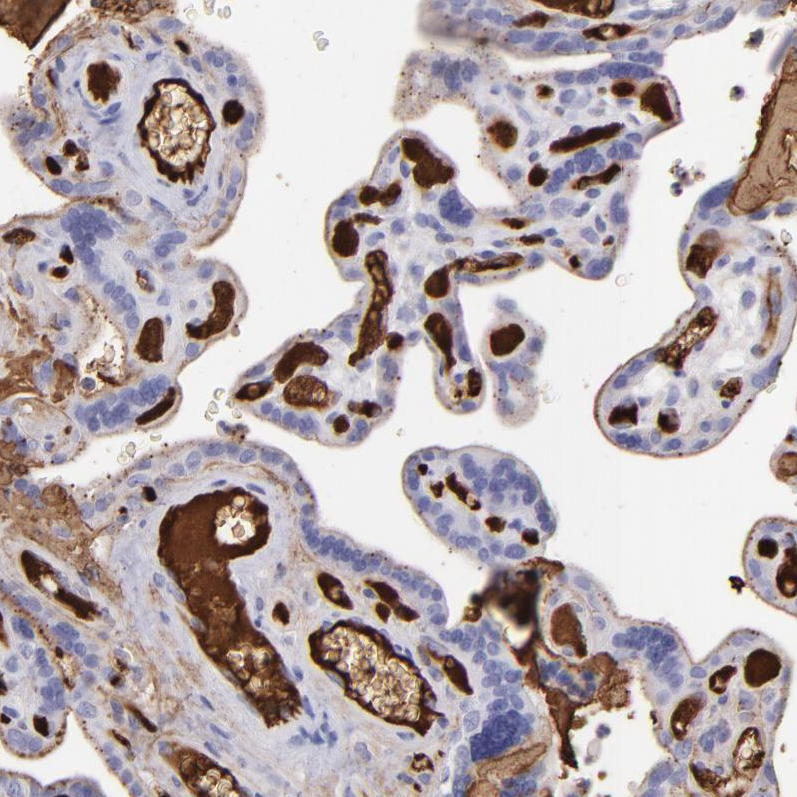

Immunohistochemical staining of human cerebral cortex, liver, placenta and rectum using Anti-FGB antibody HPA001900 (A) shows similar protein distribution across tissues to independent antibody HPA001901 (B).